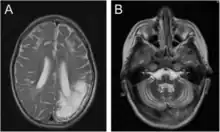

Encéphalomalacie chez un garçon de 7 ans : en imagerie par résonance magnétique (à gauche) et en tomodensitométrie (à droite)

En médecine, l'encéphalomalacie est un type d'accident vasculaire cérébral qui est un déficit neurologique soudain, d'origine vasculaire causé par un infarctus au niveau du cerveau.